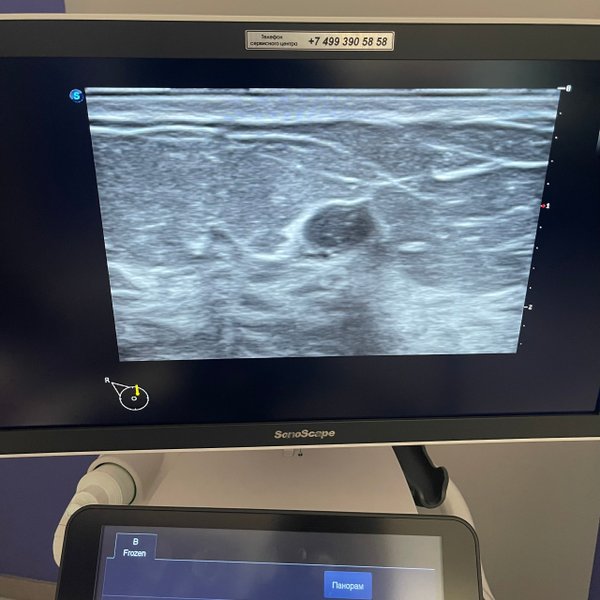

Запись на УЗИ предварительная (СРОЧНОе УЗИ ️день в день) Бородулина Наталья (Врач УЗИ, Косметология) (21.01.2025): Пациентка на #УЗИ_молочных_желез с жалобами на пальпируемое образование. Что вижу я при УЗ осмотре : солидное образование, с нечеткими границами, с кальцинатами, с питающим сосудом. BIRADS 5. Рекомендована : трепан биопсия. Результат биопсии: ЖДЕМ Если вы обнаружили у себя «шишку», не тяните время, обязательно пройдите УЗИ, нельзя пальпаторно ставить диагноз (жировик). ️Не все образования пальпируются и также бывает… — Читать дальше

, что не все то, что вы пальпируете у себя будет #образованием, поэтому лучше пройти УЗИ и спать спокойно.. ️Берегите себя! Любите себя!